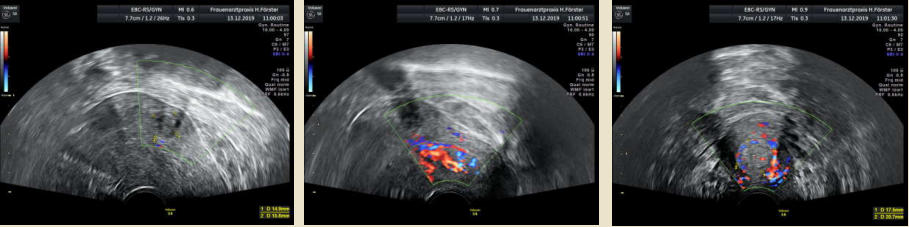

Gynäkologische Grundversorgung Frauenärztliche Krebsfrüherkennungsuntersuchung Nachsorge und supportive Therapie bei bösartigen gynäkologischen Tumoren Impfungen Brustultraschall Ultraschalluntersuchung der weiblichen Genitalorgane Psychosomatische Grundversorgung Chlamydienscreening FOB-Test (früher Hämoccult) Kontrazeption Geburtshilfliche Grundversorgung Geburtshilflicher Basisultraschall Erweiterter Basisultraschall (Organscreening) zw, 18-22.SSW Doppler/Duplexsonografie des fetomaternalen Gefäßsystems Infektionsscreening in der Schwangerschaft CTG (Kardiotokographie) Gynäkologische Grundversorgung Dies umfasst die Abklärung und Behandlung gynäkologischer Erkrankungen. Eine große Rolle dabei spielt das ärztliche Gespräch, ergänzt bei Notwendigkeit durch die gynäkologische Untersuchung oder Untersuchung der weiblichen Brust. In vielen Fällen werden noch Zusatzuntersuchungen durchgeführt (z.B. Ultraschalluntersuchungen, Abstrichentnahmen, Blutentnahmen) oder weiterführende Untersuchungen veranlasst (z.B. Röntgenuntersuchungen). >> zurück << Frauenärztliche Krebsfrüherkennungsuntersuchung Die Krebsfrüherkennungsuntersuchung der Frau ist wahrscheinlich die bekannteste Leistung unseres Fachgebietes. Ab dem Alter von 20Jahren hat jede Frau ein Anrecht auf diese jährliche Untersuchung. Dabei werden der Unterleib der Frau und ab dem Alter von 30Jahren auch die Brüste der Frau systematisch klinisch untersucht. Zusätzlich erfolgte seit vielen Jahren ein Pap-Abstrich vom Gebärmutterhals. So konnten Zellveränderungen meist rechtzeitig erkannt und behandelt werden und es wurde erreicht, daß das früher sehr häufige Zervixkarzinom (Gebärmutterhalskrebs) heute nur noch selten auftritt. Um die Qualität weiter zu verbessern erfolgte 2020 eine Neuordnung des Screenings mit Überarbeitung der Abstrichintervalle und Hinzunahme von HPV-Abstrichen ab 35 als Kassenleistung. >> zurück << Nachsorge und supportive Therapie bei bösartigen gynäkologischen Tumoren Nach Abschluss und oft auch wärend der Primärbehandlung können Probleme auftreten. Es macht also Sinn, sich in regelmäßigen Abständen zu treffen, um das weitere Vorgehen zu planen, eventuell Zusatzuntersuchungen zu veranlassen oder zusätzlich wegen der Beschwerden zu behandeln. Die Nachsorgeuntersuchungen finden anfangs engmaschig statt, später werden die Intervalle länger. >> zurück << Impfungen In Zeiten der Globalisierung, zunehmender Reisefreudigkeit und Zuwanderung werden wir wieder mit Infektionserregern konfrontiert, die wir schon als besiegt geglaubt hatten. Gleichzeitig werden wir immer älter und unser Immunsystem dabei nicht besser. Es reicht nicht, mal eben alle 10Jahre Tetanus zu impfen. Sind Sie geschützt? Wissen Sie was empfohlen ist? Bringen Sie den Impfausweis (auch den alten!!) mit. Wir prüfen Ihren Impfstatus, geben Ihnen Empfehlungen. Die gängigsten Impfstoffe haben wir auch vorrätig und können Sie impfen. >> zurück << Brustultraschall Die Ultraschalluntersuchung der Brust (Mammasonografie) kommt zur Abklärung von krankhaften Veränderungen zur Anwendung oder als Zusatzuntersuchung in der Früherkennung von Brustkrebs bei sehr dichtem Gewebe oder familiärer Vorbelastung. Sie ersetzt nicht das organisierte Mammographiescreening und ist nicht Bestandteil der normalen Krebsfrüherkennung. Es handelt sich um eine schmerzfreie Untersuchung ohne Strahlenbelastung. Die Mammasonografie  ist auch als Wunschleistung (IGeL) möglich. >> zurück << Ultraschalluntersuchung der weiblichen Genitalorgane Die Ultraschalluntersuchung der weiblichen Genitalorgane kommt zur Abklärung von krankhaften Veränderungen des weiblichen Genitales zur Anwendung. Dabei werden mit einer hochfrequenten Vaginalsonde die Organstrukturen im kleinen Becken untersucht. Die Untersuchung ist bei schlanken und sehr jungen Frauen auch vom Bauch aus möglich, die Genauigkeit ist dabei technisch bedingt aber schlechter.  Sie ist nicht Bestandteil der normalen Krebsfrüherkennung. Auch diese Untersuchung ist als Wunschleistung (IGeL) möglich. >> zurück << Psychosomatische Grundversorgung Jede Erkrankung belastet die Seele. Eine seelische Belastung macht den Körper krank. Jeder weiß das. Die Zusammenhänge zwischen dem kranken Körper und der kranken Seele beschreibt die Psychosomatik. Ein "Gordischer Knoten", der nur schwer zu zerschlagen ist, oft ein langer Weg. Ziel ist es, diese Zusammenhänge zu erkennen und den Betroffenen zu helfen ihren Weg zu finden. Oft ist die Zusammenarbeit mit einer Psychologin/ Psychologen nötig. Wichtig ist die Hilfe bei den ersten Schritten. Laufen müssen Sie selbst. >> zurück << Chlamydienscreening Das Bakterium Chlamydia trachomatis kann beim Sex übertragen werden und zu Entzündungen und sogar zur Unfruchtbarkeit führen. Deshalb bezahlen die Krankenkassen bis zum vollendeten 25.Lebensjahr allen sexuell aktiven Frauen einen Suchtest auf Chlamydien. Sie müssen lediglich eine Urinprobe abgeben. Auch in jeder Schwangerschaft wird nach Chlamydien gefahndet. Da Frauen im Normalfall auch im Alter über 25Jahren sexuell aktiv sind und noch schwanger werden wollen bieten wir die Testung auch als Wunschleistung (IGeL) an. Der Test wird dann aus einem Abstrich aus dem Muttermund entnommen, dies kann bei der Krebsfrüherkennung mit gemacht werden. >> zurück << FOB-Test (früher Hämoccult) Im Alter von 50 bis 54Jahren bezahlen die Krankenkassen allen versicherten Frauen einen Stuhltest zur Früherkennung von Darmkrebs oder seiner Vorstufen. Mit 55Jahren können Sie sich entscheiden zwischen zwei Darmspiegelungen im Abstand von 10Jahren oder der Fortführung der Stuhlteste alle 2Jahre. Natürlich kann man Stuhlteste auch zwischen den Darmspiegelungen machen lassen oder auch bei Frauen jünger als 50. Wir bieten dies als Wunschleistung (IGeL) unseren Patienten an. >> zurück << Kontrazeption Ein selbstbestimmtes Leben als Frau ist bei uns in Deutschland eine Selbstverständigkeit. Das war nicht immer so.  Kinder-Küche-Kirche hieß es früher, damals, in der guten alten Zeit. Das ist zum Glück vorbei. Und begonnen hat alles mit der Pille. Frauen konnten endlich über ihren Körper selbst bestimmen, ohne Angst ihre Liebe leben.  Aber die Pille ist nicht alles. Viele Märchen sind im Umlauf, Fehlinformation. Aber auch fehlendes Wissen zu Risiken.  Wir beraten Sie gern. >> zurück << Geburtshilfliche Grundversorgung In der Schwangerenberatung werden die werdenden Muttis gemäß den geltenden Mutterschaftsrichtlinien vom Anfang der Schwangerschaft bis zur Abschlussuntersuchung (6-8 Wochen nach der Geburt) betreut. >> zurück << Geburtshilflicher Basisultraschall Nach Vorgabe der Mutterschaftsrichtlinie sind sind in der Schwangerschaft 3 Ultraschalluntersuchungen vorgesehen. Diese finden in der 8.-12. SWW, in der 18,- 22. SSW und in der 28.-32.SSW statt. Dabei werden der Zustand des Embryos/ Feten, des Fruchtwassers und der Plazenta beurteilt. >> zurück << Erweiterter Basisultraschall (Organscreening) zw. 18-22.SSW Bei der zweiten Ultraschalluntersuchung (zw.18.-22. SSW) erfolgt ein erweitertes Screening mit Beurteilung der Organstrukturen des Kindes. Diese Untersuchung ist Kassenleistung, kann aber bei Wunsch auch Abgewählt werden, dann wird nur der Basisultraschall durchgeführt. >> zurück << Doppler/Duplexsonografie des fetomaternalen Gefäßsystems Bei Aüffälligkeiten im Schwangerschaftsverlauf oder auch bei bestimmten Vorerkrankungen oder Erkrankungen in einer früheren Schwangerschaft kann es notwendig sein die Durchblutung des Mutterkuchens und der Gefäße des Kindes zu Untersuchen. Hier kommt das Dopplerverfahren als Erweiterung des normalen geburtshilflichen Ultraschalls zum Einsatz. Dies erlaubt eine schnelle Zustandsbeurteilung des Kindes pepaart mit einer zeitlich begrenzten Vorhersage über die weitere wahrscheinliche Entwicklung. Bei entsprechender Indikation ist diese Untersuchung als Kassenleistung abrechenbar. >> zurück << Infektionsscreening in der Schwangerschaft Die Suche nach Krankheitserregern im Krankheitsfall ist Kassenleistung. Routinemäßig prüfen wir Ihren Schutz vor Röteln und Windpocken , in jeder Schwangerschaft erfolgt ein Test auf Chlamydien. Zusätzlich empfehlen wir jeder Schwangeren einen Test auf eine Besiedelung mit Gruppe-B-Streptokokken vor der Geburt. Diese Streptokokken können zu schweren Atemwegsinfektionen des Neugeborenen führen. Eine vorbeugende Behandlung bei positivem Test kann dann unter der Geburt erfolgen. Bei Wunsch kann auch ein erweitertes Erregerscreening über unser Labor erfolgen (Wunschleistung). Eine wichtige Rolle spielt auch die Kontrolle auf einen Schutz gegen eine Toxoplasmoseinfektion. Bei fehlendem Schutz empfielt sich die regelmäßige Testung aus dem Blut auf eine frische Infektion. Auch dies ist eine Privatleistung, wird aber von den meisten Kassen erstattet. Eine nicht erkannte und somit nicht behandelte Erstinfektion in der Schwangerschaft kann zu schweren Schäden beim Kind führen. >> zurück << CTG Ab etwa der 30.Schwangerschaftswoche können wir bei Notwendigkeit im Ramen der Schwangerschaftsvorsorge die kindlichen Herztöne (Kardiographie) und simultan dazu die die Spannung der mütterlichen Bauchdecke (Wehenschreiber, Tokographie) graphisch darstellen. Das nennt man zusammen Kardiotokographie oder kurz einfach CTG. Die Auswertung des CTG‘s erfolgt nach dem Fisher-Score (Punkte-System) sowie nach qualitativen Kriterien und erlaubt uns eine gute Zustandsbeurteilung des Kindes in den späteren Schwangerschaftswochen. >> zurück <<